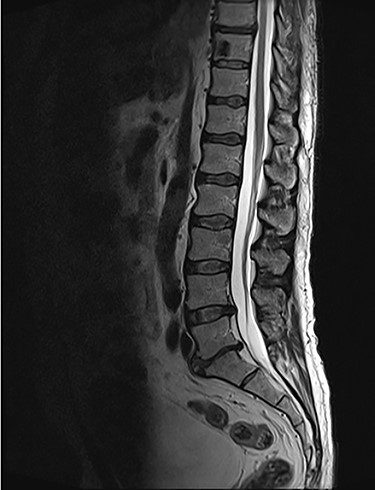

Sagittal T2-weighted magnetic resonance image (T2W MRI) with T4 metastatic epidural spinal cord compression (MESCC) and a synchronous T10 lytic lesion.

Sagottal T2W MRI showing synchronous lytic lesions in T10 & L3 vertebral bodies.